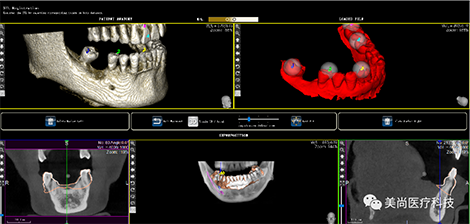

A.将CBCT数据导入软件中

B.绘制下颌神经管

E.软件上修复体设计

C.添加模型数据

D.图像拟合

F.选择牙位添加种植体

G.选择合适的导环全程或者定位完成植体设计

H.自动生成种植计划报告

1.CT数据导入

2.成像预览

3.添加放射导板数据

4.尽量让每一对匹配点角度一致

5.种植模拟设计

6.自动生成报告及进行数据输出